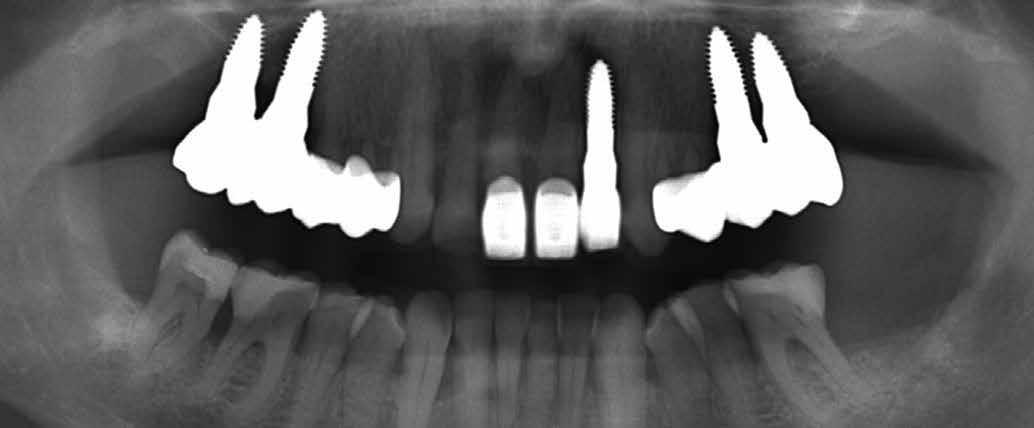

A pótlásra szoruló fogat, vagy fogakat minden esetben legalább egy évvel a fogpótlást megelőzően eltávolítottuk. Ezen esetek egyikében sem végeztünk alveolus vagy állcsontgerinc prezervációt az eltávolítás során, illetve minden páciens jó szájhigiéniával rendelkezett. Egy kivételével minden páciensnél radiológiai analízist végeztünk CBCT-vel,

digitális implantátumtervezés követett (SICAT és Sidexis, mindkettő Dentsply Sirona; 1. ábra).

Mind a hat implantátum esetén kétlépcsős műtétet végeztünk. Minden sebészeti eljárást bódítás, illetve preoperatív szisztémás antibiotikus terápia nélkül végeztünk. A négy eset közül kettőnél leukocitában és vérlemezkében gazdag fibrint (L-PRF) alkalmaztunk a beavatkozás során (IntraSpin, BioHorizons; 2. táblázat). Minden esetben a pontos CERALOG menetvágási (maximum 15 ford./perc) és fúrási (maximális fúrási fordulatszám: 550–800 ford./perc) protokollt követtük. Az összes implantátumot manuálisan helyeztük be 35 Ncm maximális nyomatékkal. Az implantátumokba PEEK zárócsavar került (2. ábra). A lágyszövetet atraumatikus, felszívódó varrattal, szorosan zártuk/összevarrtuk. A műtétek után szövődmények nem jelentkeztek. A pácienseket arra kértük, hogy a műtét utáni héten naponta kétszer öblögessenek klórhexidinnel (PERIO-AID, 0,05%, DENTAID). Az alsó állcsontnál három hónapos, a felső állcsontnál öt hónapos gyógyulási időt vettünk figyelembe. Három hónap (1. eset) és öt hónap (2., 3. és 4. eset) elteltével a műtétek második stádiumát helyi érzéstelenítés mellett végeztük. A gyógyu-

lási csavarokat (PEEK titáncsavarral) maximum 15 Ncm-rel húztuk meg (3–6. ábra). Az összes implantátum kiváló stabilitást mutatott (a mérésekhez Periotestet használtunk, a Medizintechnik Gulden jóvoltából), és teljesen osszeointegrálódott. Ezt a radiológiai vizsgálatok is megerősítették.

2. a–d ábra: PEEK zárócsavarok az implantátumokba helyezve, 1. eset (a). 2. eset (b). 3. eset (c), 4. eset (d). 3. a–b ábra: Röntgenfelvételek három hónap után (a) és a gyógyulási csavarok behelyezve (b, 1. eset). 4. a–b ábra: Röntgenfelvételek öt hónappal később (a) és a gyógyulási csavarok behelyezve (b, 2. eset). 2. táblázat: Az implantátum tulajdonságai.